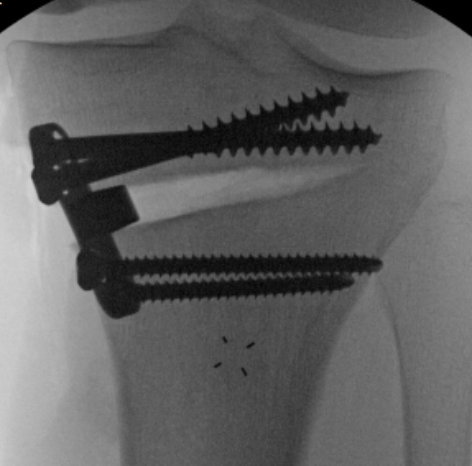

Assessing Union

Xray

Some reossification and evidence of union

MRI

Reossification and evidence of bony bridging

CT

Evidence of bony union on CT

Results

- 87 patients undergoing screw fixation for unstable OCD

- 76% union rate at 2 years

- no difference between open or closed growth plates

- increased nonunion for LFC OCD